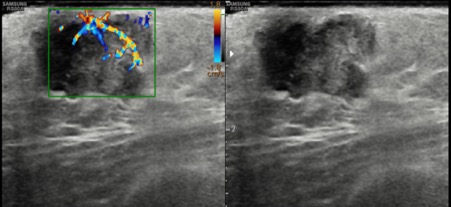

Bilateral Digital mammography , Craniocaudal (CC) and Mediolateral oblique (MLO) view revealed an irregular , high density mass with indistinct margin in retroareolar region with retracted nipple. No microcalcifications was seen. No significant axillary lymph nodes were present. Ultrasound of left breast showed an irregular, heterogeneously hypoechoic mass with indistinct margin and mild posterior acoustic enhancement, measuring about 2.5x1.9x1.3cm in retroareolar region. Internal vascularity was increased on colour doppler. On strain sonoelastogram, the mass showed increased stiffness suggestive of hard consistency. The imaging features are highly suspicious for male breast cancer and thus the mass was classified as BIRADS category 5 lesion and Ultrasound guided biopsy was advised. Patient underwent left modified radical mastectomy and final histopathological report was Invasive Lobular carcinoma. No nipple or lymphovascular invasion was identified.